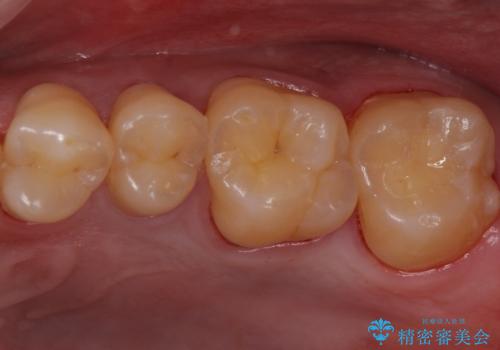

欠けてしまった奥歯 セラミッククラウンとセラミックインレーによるむし歯治療